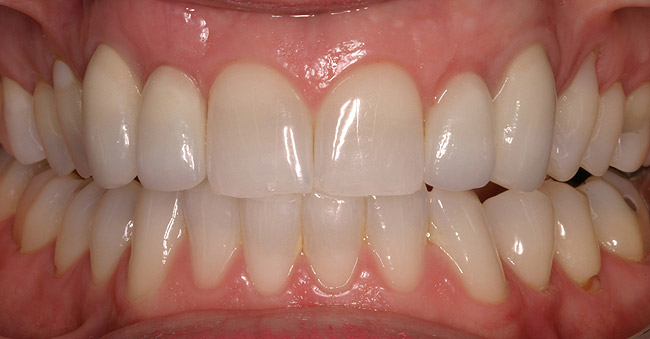

Figure 5d  Completed, porcelain-fused-to-gold implant restorations, custom gold abutments, lingual-set screw-retention, Kerr Extrude¬Æ light-body crown-abutment seal.

Figure 5d

Figure 5e  Completed, porcelain-fused-to-gold implant restorations, custom gold abutments, lingual-set screw-retention, Kerr Extrude¬Æ light-body crown-abutment seal.

Figure 5e

Figure 5f  Completed, porcelain-fused-to-gold implant restorations, custom gold abutments, lingual-set screw-retention, Kerr Extrude¬Æ light-body crown-abutment seal.

Figure 5f

Figure 5g  Completed, porcelain-fused-to-gold implant restorations, custom gold abutments, lingual-set screw-retention, Kerr Extrude¬Æ light-body crown-abutment seal.

Figure 5g